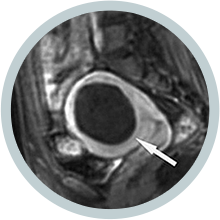

• 시술 진후 시술 직후

하이푸 시술 직후

MRI 조영증강영상에

뚜렷하게 혈류가 차단된

비관류 구역을 보임